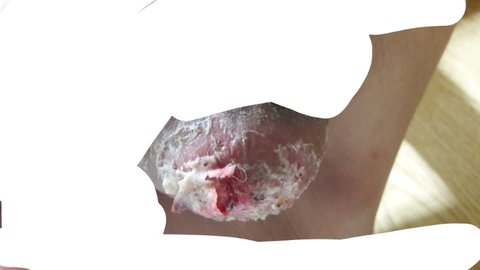

너무 혐오스러워서 미방사진 올렸어 나 다리 어렸을때 교통사고 심하게 당하고 (잘렸었음) 수술6번정도 하고 해서 되게 기괴하단말임 그리고 아프기도 너무 아파서 자퇴했는데 완전 히키코모리처럼 지내다가 아까 스트레스땜시 먹고싶어서 뭐 사러갔단 말이야 걷는 도중에 자꾸 아프길래 뭐지하면서 인상 쓴 상태로 빨리 오고 씻고 나와서 바닥 밟았는데 핏자국이 나있더라고 봤더니

(혐오사진 주의 피 주의) 제발 진짜 혐오니까 싫어하는 사람은 안봤으면 좋겠어 내 다리가 정상적인 사람의 다리가 아니야 징그러우니까 주의해줘

ㅋㅋ... 매일 걸어다닐땐 저부분 굳은살 배겨서 피는 안났는데 몇개월만에 나가니까 찢어졌어 그래도 10분 걸었는데 저정도면 너무 심한거 아니냐 나 살지말라는건가ㅋㅋ 우울하다 그리고 저번에 병원갔는데 병원교수님이 다리 잘라야 된다더라 게다가 이 교수님 나 교통사고 당하고 수술 집도하신 분임 징그러운 사진 보게 해서 미안 그냥 신세한탄 하고싶은데 마땅한 사람이 없어서 커뮤니티 에서라도 털어놓으려고 글 썼어